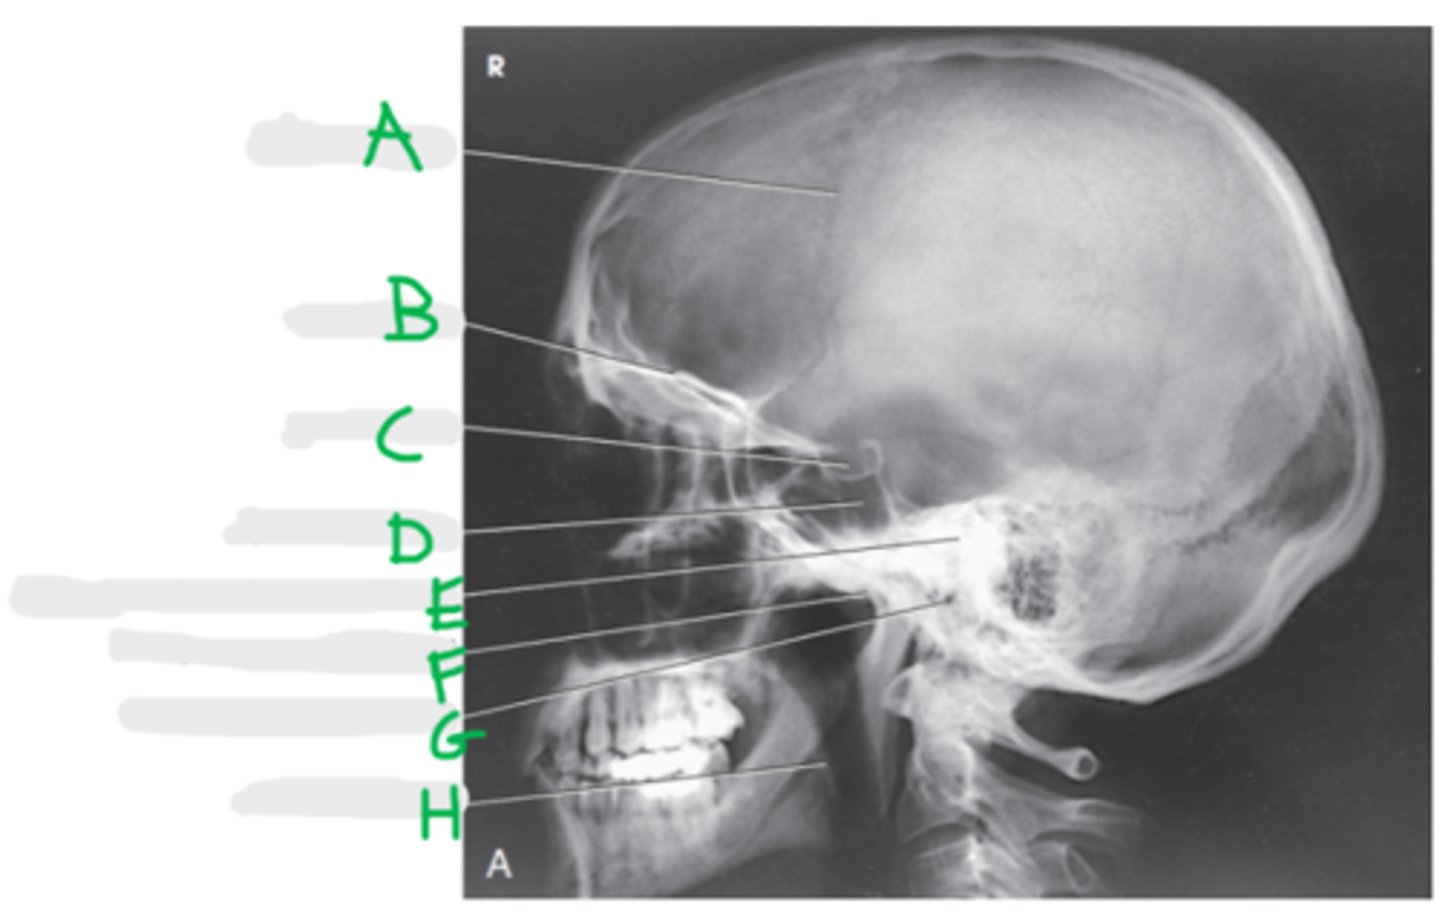

Coronal Suture

A

Orbital roof

B

Sella turcica

C

Sphenoid sinus

D

Petrous portion of temporal bone

E

Temporomandibular joint

F (jt)

EAM

G

Mandibular rami

H

Lateral Skull

What projection is this?

CR 2 inches superior to EAM

What is the CR for a lateral skull?

Interpupillary line (IPL)

What line is perpendicular to the IR for a lateral skull?

IOML and MSP

What line is parallel to the IR?

BOTH!

What lateral do we do for a skull?